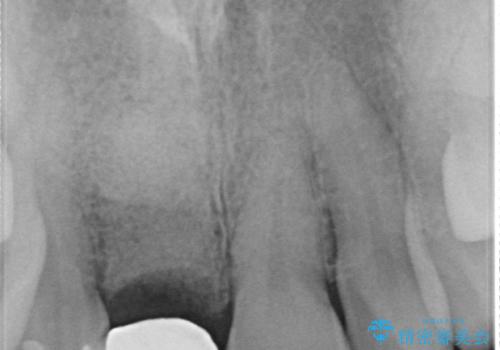

審美的・機能的に良好な位置に埋入するには、骨量が十分ではなかったため骨の造成を併用したインプラント埋入外科手術を行います。

前歯のインプラントを審美的に仕上げるには、インプラント周囲に十分な骨の量と厚みのある歯肉、そして埋入位置の精密な位置付けが重要です。